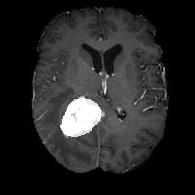

We argue that the sub-optimal paradigm of processing different abstractions within a single CNN pipeline can be remedied through the effective processing of information in a structured manner. Consequently, we devise strategies for disentangling the edge and texture information within a single training pipeline. Figure 2 illustrates how our proposed module, dubbed EG-CNN, can be paired with any existing CNN encoder-decoder to improve segmentation quality near intensity edges. We have applied our EG-CNN to the tasks of brain and liver tumor segmentation in medical images (Figure 3).

(1) Brain MR (2) Liver MR (3) Liver CT (4) Lung CT